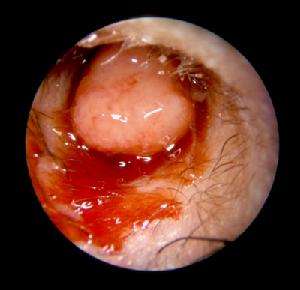

鬆弛部或緊張部後上方有邊緣性穿孔。從穿孔處可見鼓室內有灰白色鱗屑狀或豆渣樣物質,奇臭。